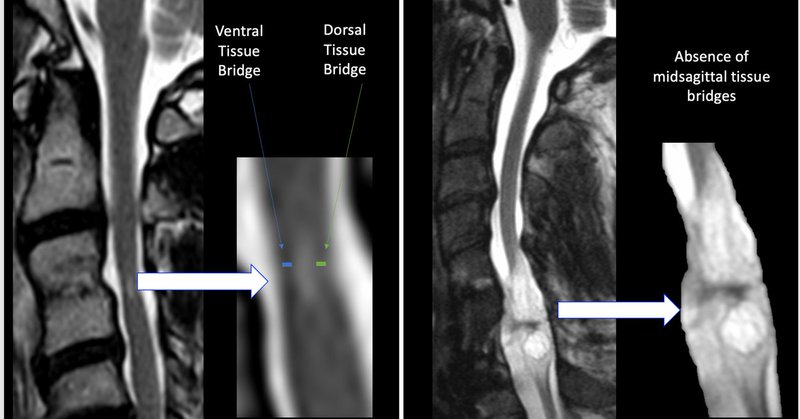

I am very excited to announce the publication of my first lead author manuscript! Many thanks to my amazing mentor @DrAndrewCSmith and the team at the Rocky Mountain VA for the support and collaboration! Check it out! https://t.co/Tl75C8rw5n @CURehabSci

Spinal Cord - The presence or absence of midsagittal tissue bridges and walking: a retrospective cohort study in spinal cord injury

Very happy to share our latest pub, a case-series exploration on tissue bridges and TSS for SCI UE recovery! This is @jordanrobcon's first paper as a PhD student in @CURehabSci, and a fun collaboration with @WesleyThorPT, @CandyTefer1216, @DrKenWeber, @DarioPfyffer. (1/2)